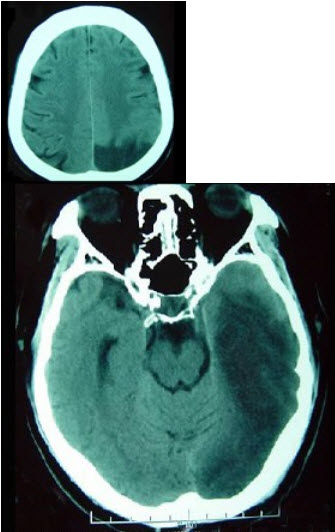

女性,77岁,有糖尿病史3年,高血压病史5年因左侧肢体无力1天入院。查体神志清楚,右侧同向偏盲,右侧轻度中枢性面瘫,右侧肢肌力4级,行头颅CT出现如图所示病灶。

(单选题)最可能的诊断是( )

A:颅脑肿瘤

B:颅内感染

C:脑梗死

D:多发性硬化

E:脑出血

第2题,共2个问题

(单选题)该病灶为哪根血管支配( )

A:大脑后动脉

B:脉络膜前动脉

C:大脑中动脉

D:颈内动脉

E:大脑前动脉